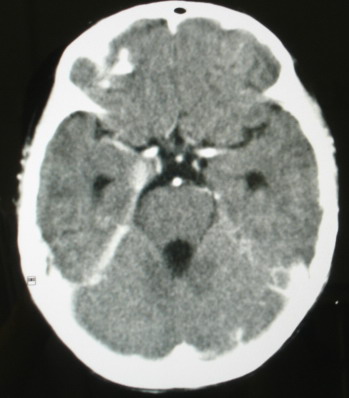

ct意见:1、颅内血管畸形。2、右侧海绵窦血管瘤(颈内动脉海绵窦段动脉瘤)。3、脑萎缩。4、建议mr或dsa.

支持:颅内血管畸形伴右侧海绵窦血管瘤(颈内动脉海绵窦段动脉瘤)。

考虑右侧海绵窦瘘,

右侧海绵窦血管瘤

右侧海绵窦血管瘤伴右侧海绵窦漏形成(由于右眼上静脉较左侧增粗。故考虑)。